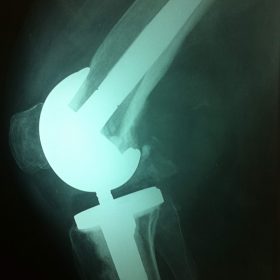

Σε αυτό το σημείο η Αρθροπλαστική Γονάτου αποτελεί μονόδρομο.